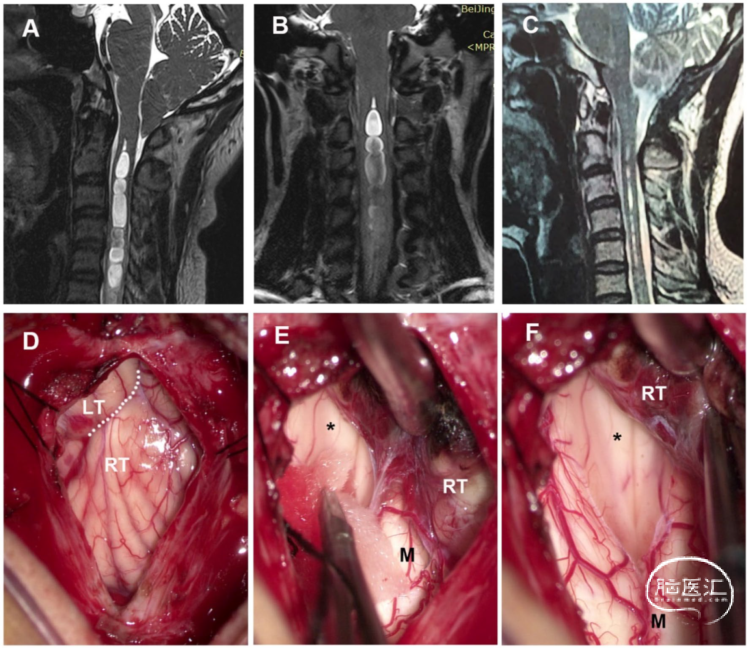

女性,32岁,有1年的枕部疼痛和左肢麻木病史。术前MRI显示,SM向上延伸至延髓,第四脑室未扩张。后颅窝探查显示,扁桃体居中,占据枕骨大孔,并覆盖Magendie孔。同时观察到一层半透明的膜覆盖在Magendie的孔上。进行软膜下扁桃体切除术,移除蛛网膜隔膜(箭头所示)。术后MRI显示,SM的大小显著减小。术后症状完全缓解(图3)。

图3. 部分交通型CM-SM病例。A. 术前MRI-T2矢状位加权成像。注意SM向上延伸至延髓,无第四脑室扩张。B. 高分辨率MR显示,第四脑室和SM(黑色箭头)之间在一定水平上有一个可检测的通道。C. 术后MRI显示,SM明显减少。D. 硬脑膜切口显示,扁桃体居中,扁桃体占据枕骨大孔,并覆盖Magendie孔。E. 可见Magendie孔,并观察到半透明隔膜(箭头)。F. 进行软膜下扁桃体切除术,并移除蛛网膜隔膜(如箭头所示)。